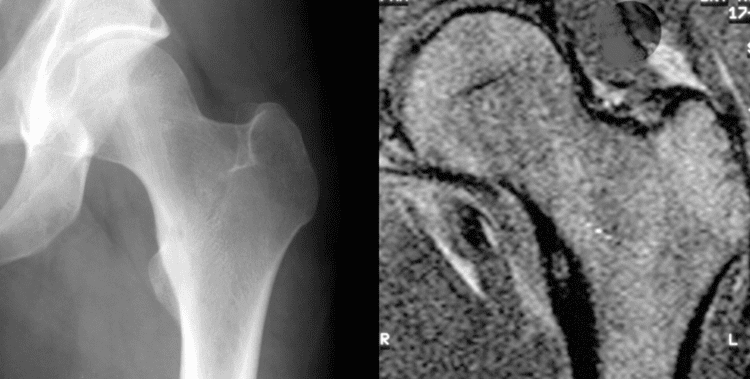

Radiographs in osteoid osteoma typically show a round lucency, containing a dense sclerotic central nidus (the characteristic lesion in this kind of tumor), surrounded by sclerotic bone. The nidus is seldom larger than 1.5 cm.

The lesion can in most cases be detected on CT scan, bone scans and angiograms. Plain radiographs are not always diagnostic. MRI adds little to the CT findings which are useful for localisation. Radionuclide scanning shows intense uptake which is useful for localisation at surgery using a hand held detector, and for confirmation that the entire lesion has been removed.